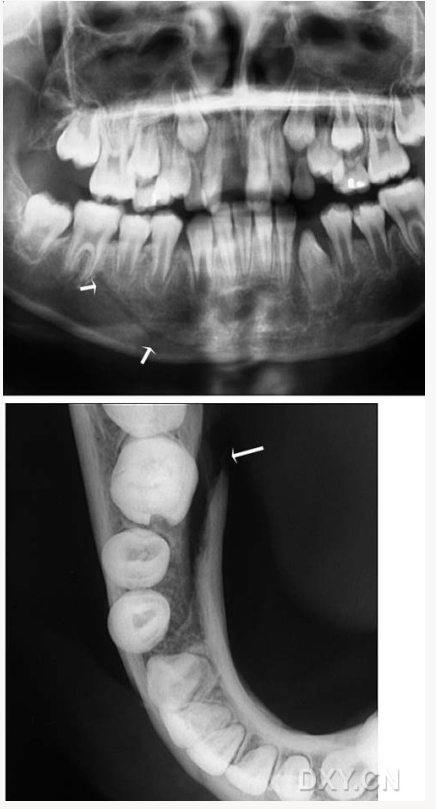

成釉細胞瘤

涎石病

骨髓炎

頜骨骨折